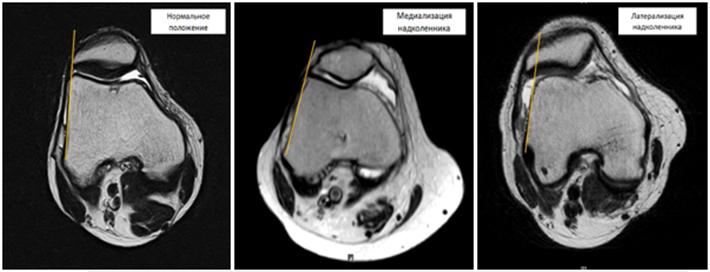

Медиализация (смещение внутрь) и латерализация (смещение наружу) надколенника (см. фото) – наиболее часто встречающееся осложнение дисфункции капсульно-связочного аппарата коленного сустава. Данное заболевание сопровождается незначительными болями и «хрустом» в области коленного сустава, которые возникают при сгибании коленного сустава и при длительном сидении с согнутыми в коленях ногами. Незначительные, вначале, боли со временем усиливаются, приобретают ноющий характер и стремление пациентов сидеть с вытянутыми (разогнутыми в коленях) ногами. Данное заболевание приводит к развитию артроза надколенниково-бедренного (пателло-феморального) сустава и значительному снижению качества жизни.

Дислокация (медиализация или латерализация) надколенника могут быть как врожденными, так и приобретенными. Врожденная дислокации надколенника обусловлена неправильным развитием собственной связки надколенника и неправильным формированием точки прикрепления этой связки, что приводит к нарушению оси скольжения надколенника по бедренной кости и его смещению. Приобретенная дислокация надколенника развивается в результате травм области коленного сустава, которые приводят к полному или частичному повреждению наружной или внутренней натягивающей связки надколенника. Обычно повреждения натягивающих связок надколенника не диагностируются, а боли проходят через 5-7 дней после травмы. Поврежденная связка срастается с формированием рубца, который со временем растягивается в результате чего нарушается равнодействие боковых сил, действующих на надколенник, и последний смещается или наружу, или во внутрь.